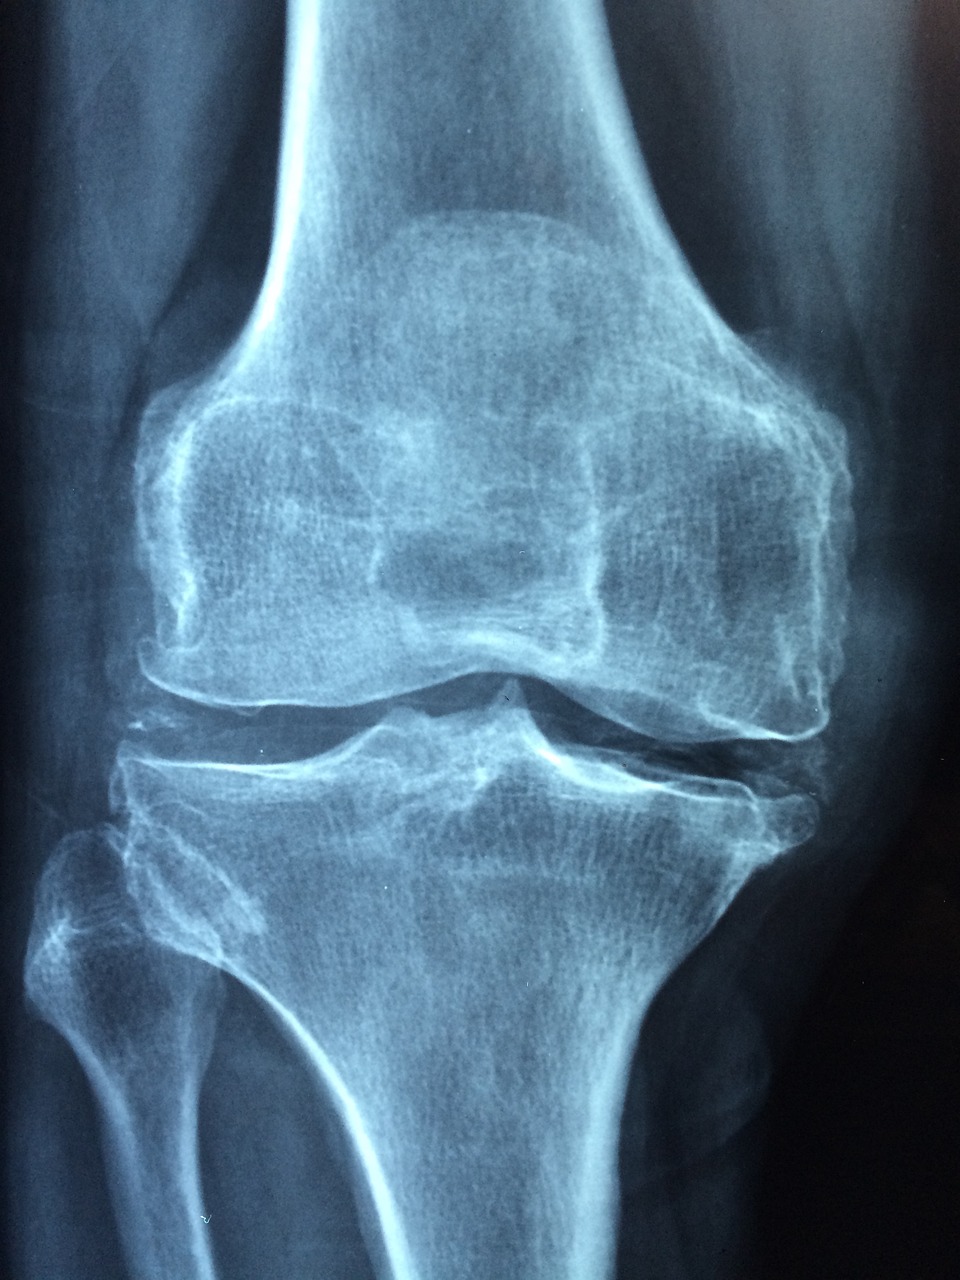

골다공증은 뼈의 밀도가 낮아지고 강도가 약해지는 질환이에요. 일반적으로 뼈에 충격을 주는 운동이 골밀도에 좋다고 알려져 있지만, 수영은 '저충격'이면서도 '근육 강화'와 '혈액 순환 촉진'을 통해 뼈 건강을 지켜준답니다!